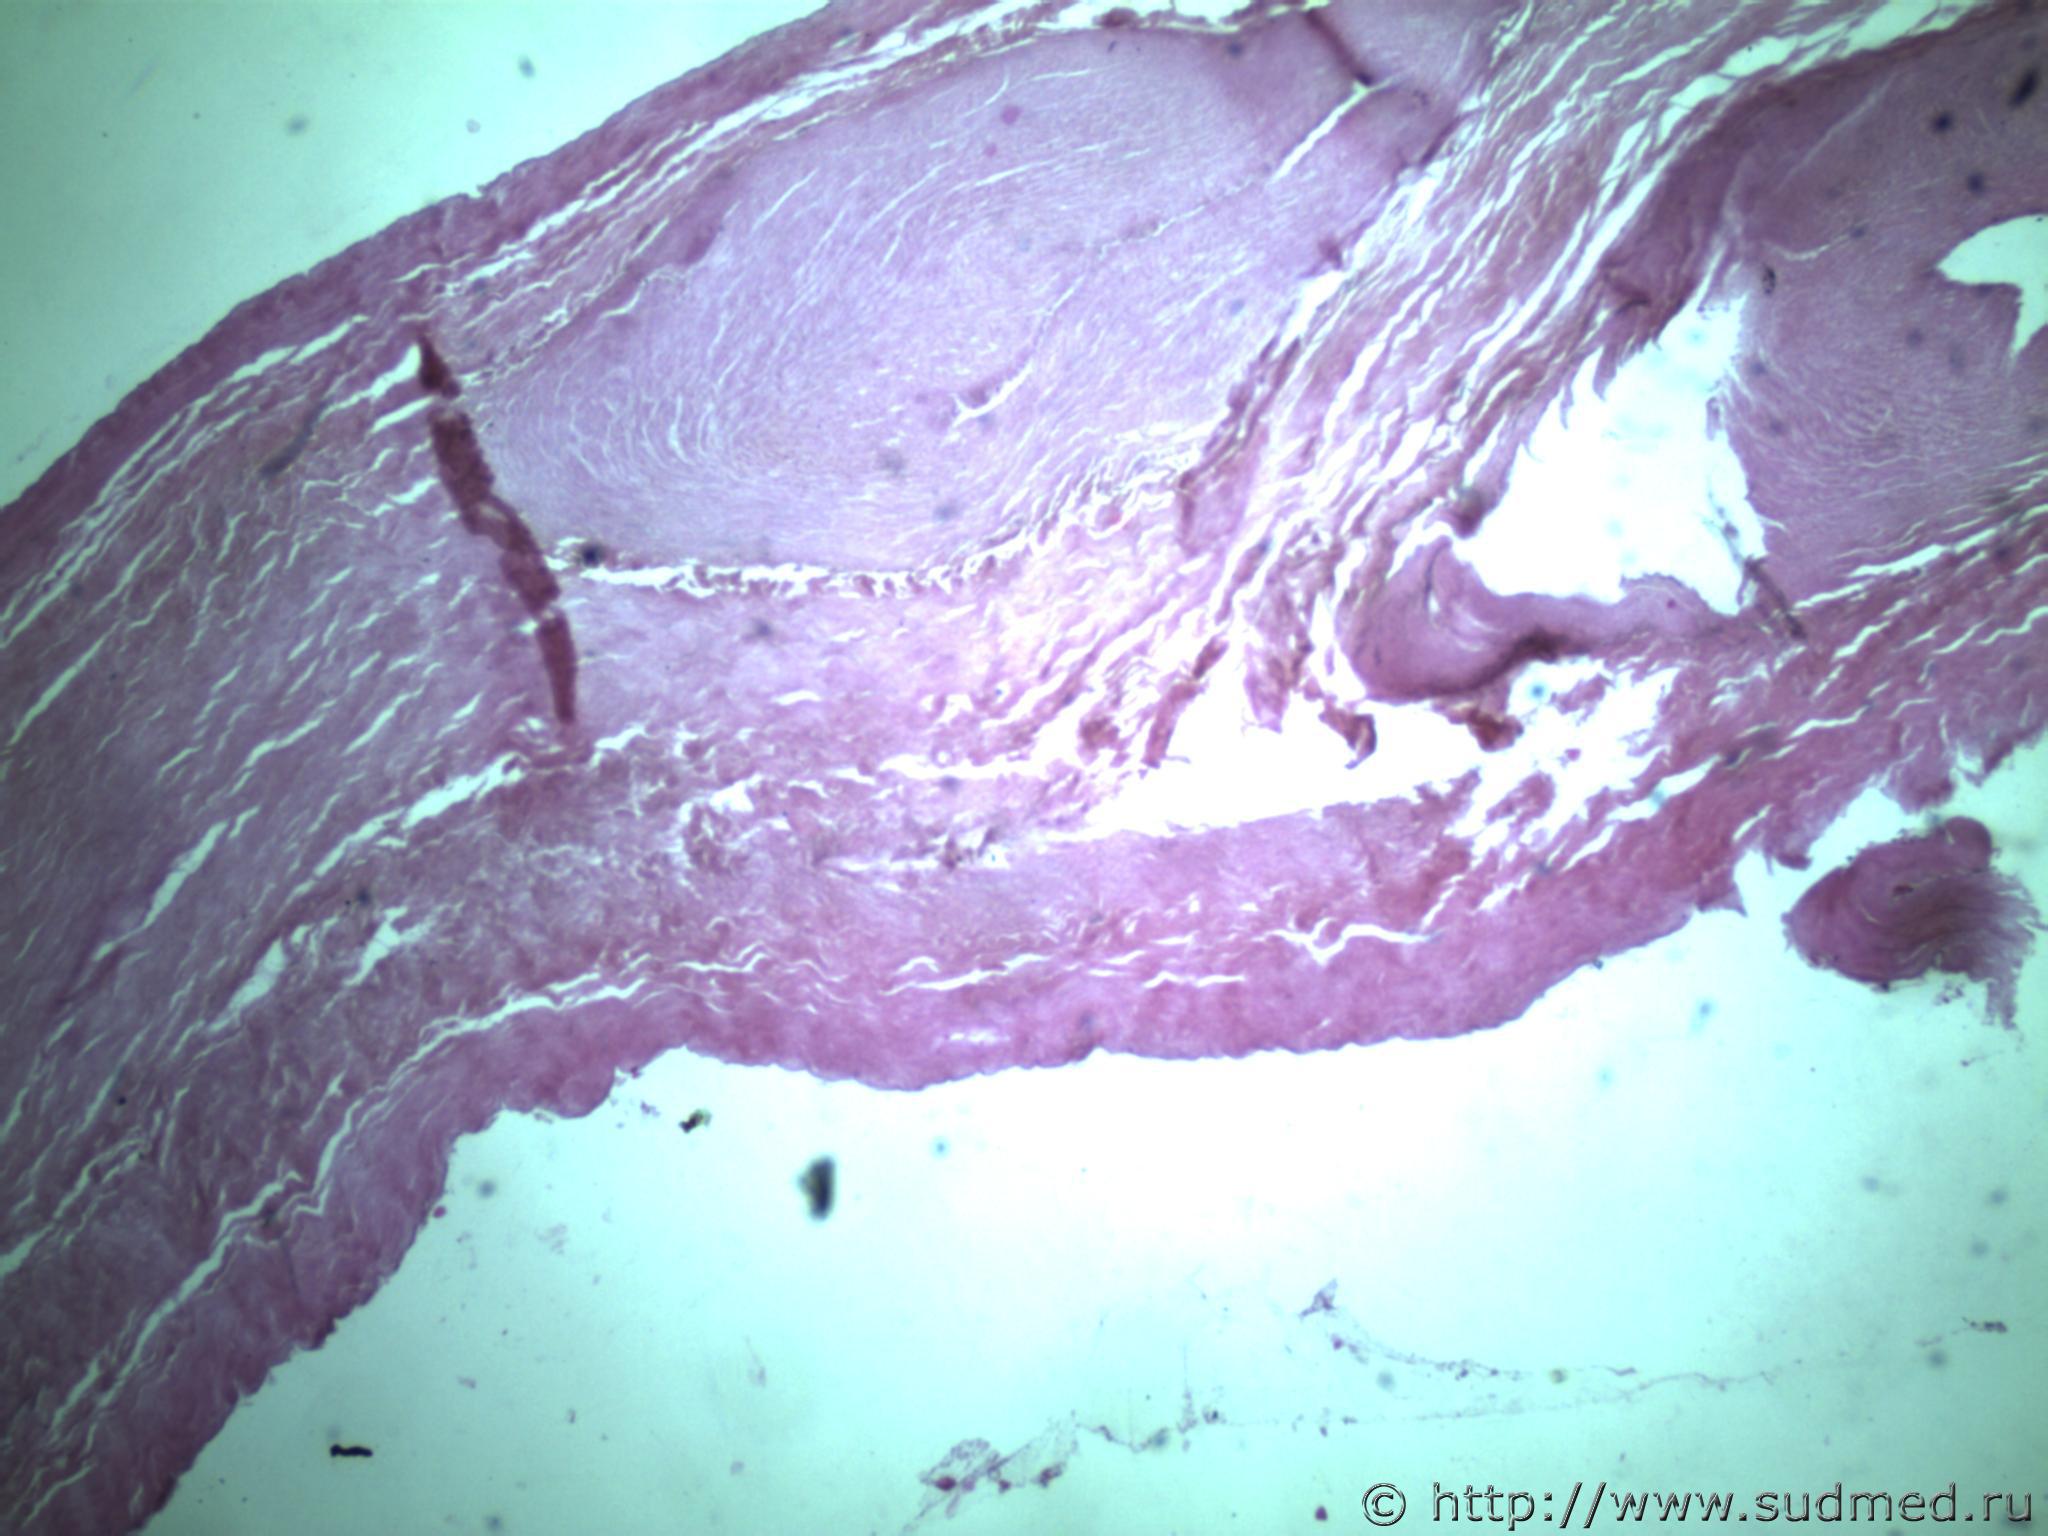

всем здравствуйте. хотела бы знать ваши мнения. провожу экспертизу. препараты как и труп новорожденного гнилые либо в аутолизе страшном. в легком картина такова, что ткань "плотная". просвет различимых альвеол в виде щелей и по всем полям зрения элементы околоплодных вод. одна артерия пуповины спазмирована. остальные сосуды непонятно : просвет их спавшийся но без признаков спазма. они как будто сплющены. да и сама пуповина в виде тонкого тяжа, видно из-за гнилостных изменений. под тмо спинного мозга признаки кровоизлияния, как и в коже с шеи. в коже головы с полнокровием отдельных сосудов. мать утверждает что ребенок после родов не сразу но все же шевелился и кричал. хотя перед этим он выпал у нее из матки на пол, ударившись головой. и со слов матери у него была пена изо рта и он хрипел.

Микрофото лёгких показать можете ?

сегодня сфоткаю конечно. но не факт что будут качественные фотки. плавательная проба - "сомнительная".

Судебная медицина - Прикрепленное изображение Судебная медицина - Прикрепленное изображениеСудебная медицина - Прикрепленное изображениеСудебная медицина - Прикрепленное изображениеСудебная медицина - Прикрепленное изображение

ну вот как то так. там еще и фотки пуповины.

Плохо,материал гнилой.

Остановился бы на дышавшем лёгком.

5 фото в сообщении №4 и 8 фото в сообщении №5 не наводит ли на мысль о дышавшем лёгком ?

Про остальные фото молчу,там или ничего не видно или же есть оптически пустые пузыри,что вероятнее всего,проявления гниения.